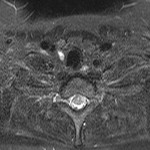

[画像診断]第17回肝血流動態イメージ研究会 Gd-EOB造影肝細胞相で集積増加するHCCについて 2011-03-01

[詳細は「タカ派の画像診断医」へ)